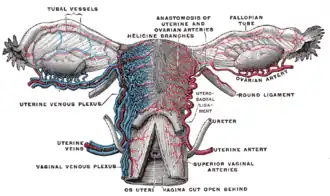

| Vascularização | artéria ovariana, artéria uterina, helicine branches of uterine artery |

Vasos do útero, vistos por trás

Vasos do útero, vistos por trás -

As artérias dos órgãos internos femininos, vistas por trás

As artérias dos órgãos internos femininos, vistas por trás -